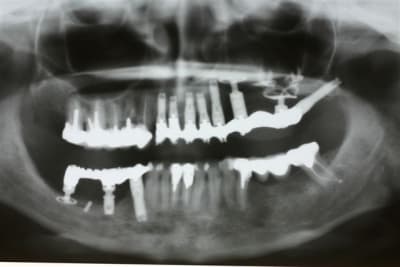

1 Radiographie panoramique avant implantation.

Les deux implants du haut ont été perdus.

2La greffe autologue prélevée à la hanche à totalement fondu.

Il ne reste que la vis d'ostéosynthèse qui avait servi à fixer le greffon.

3 Radiographie Panoramique de la correction

4 Utilisation d'un implant à plaque.

La vis d'ostéosyntèse impossible à dévisser a dû être coupée.

5 Un bridge transitoire a été mis en place deux jours après la pose des implants

et roule mais pour la pérennité du cas une équilibration due l'ensemble de la bouche .....